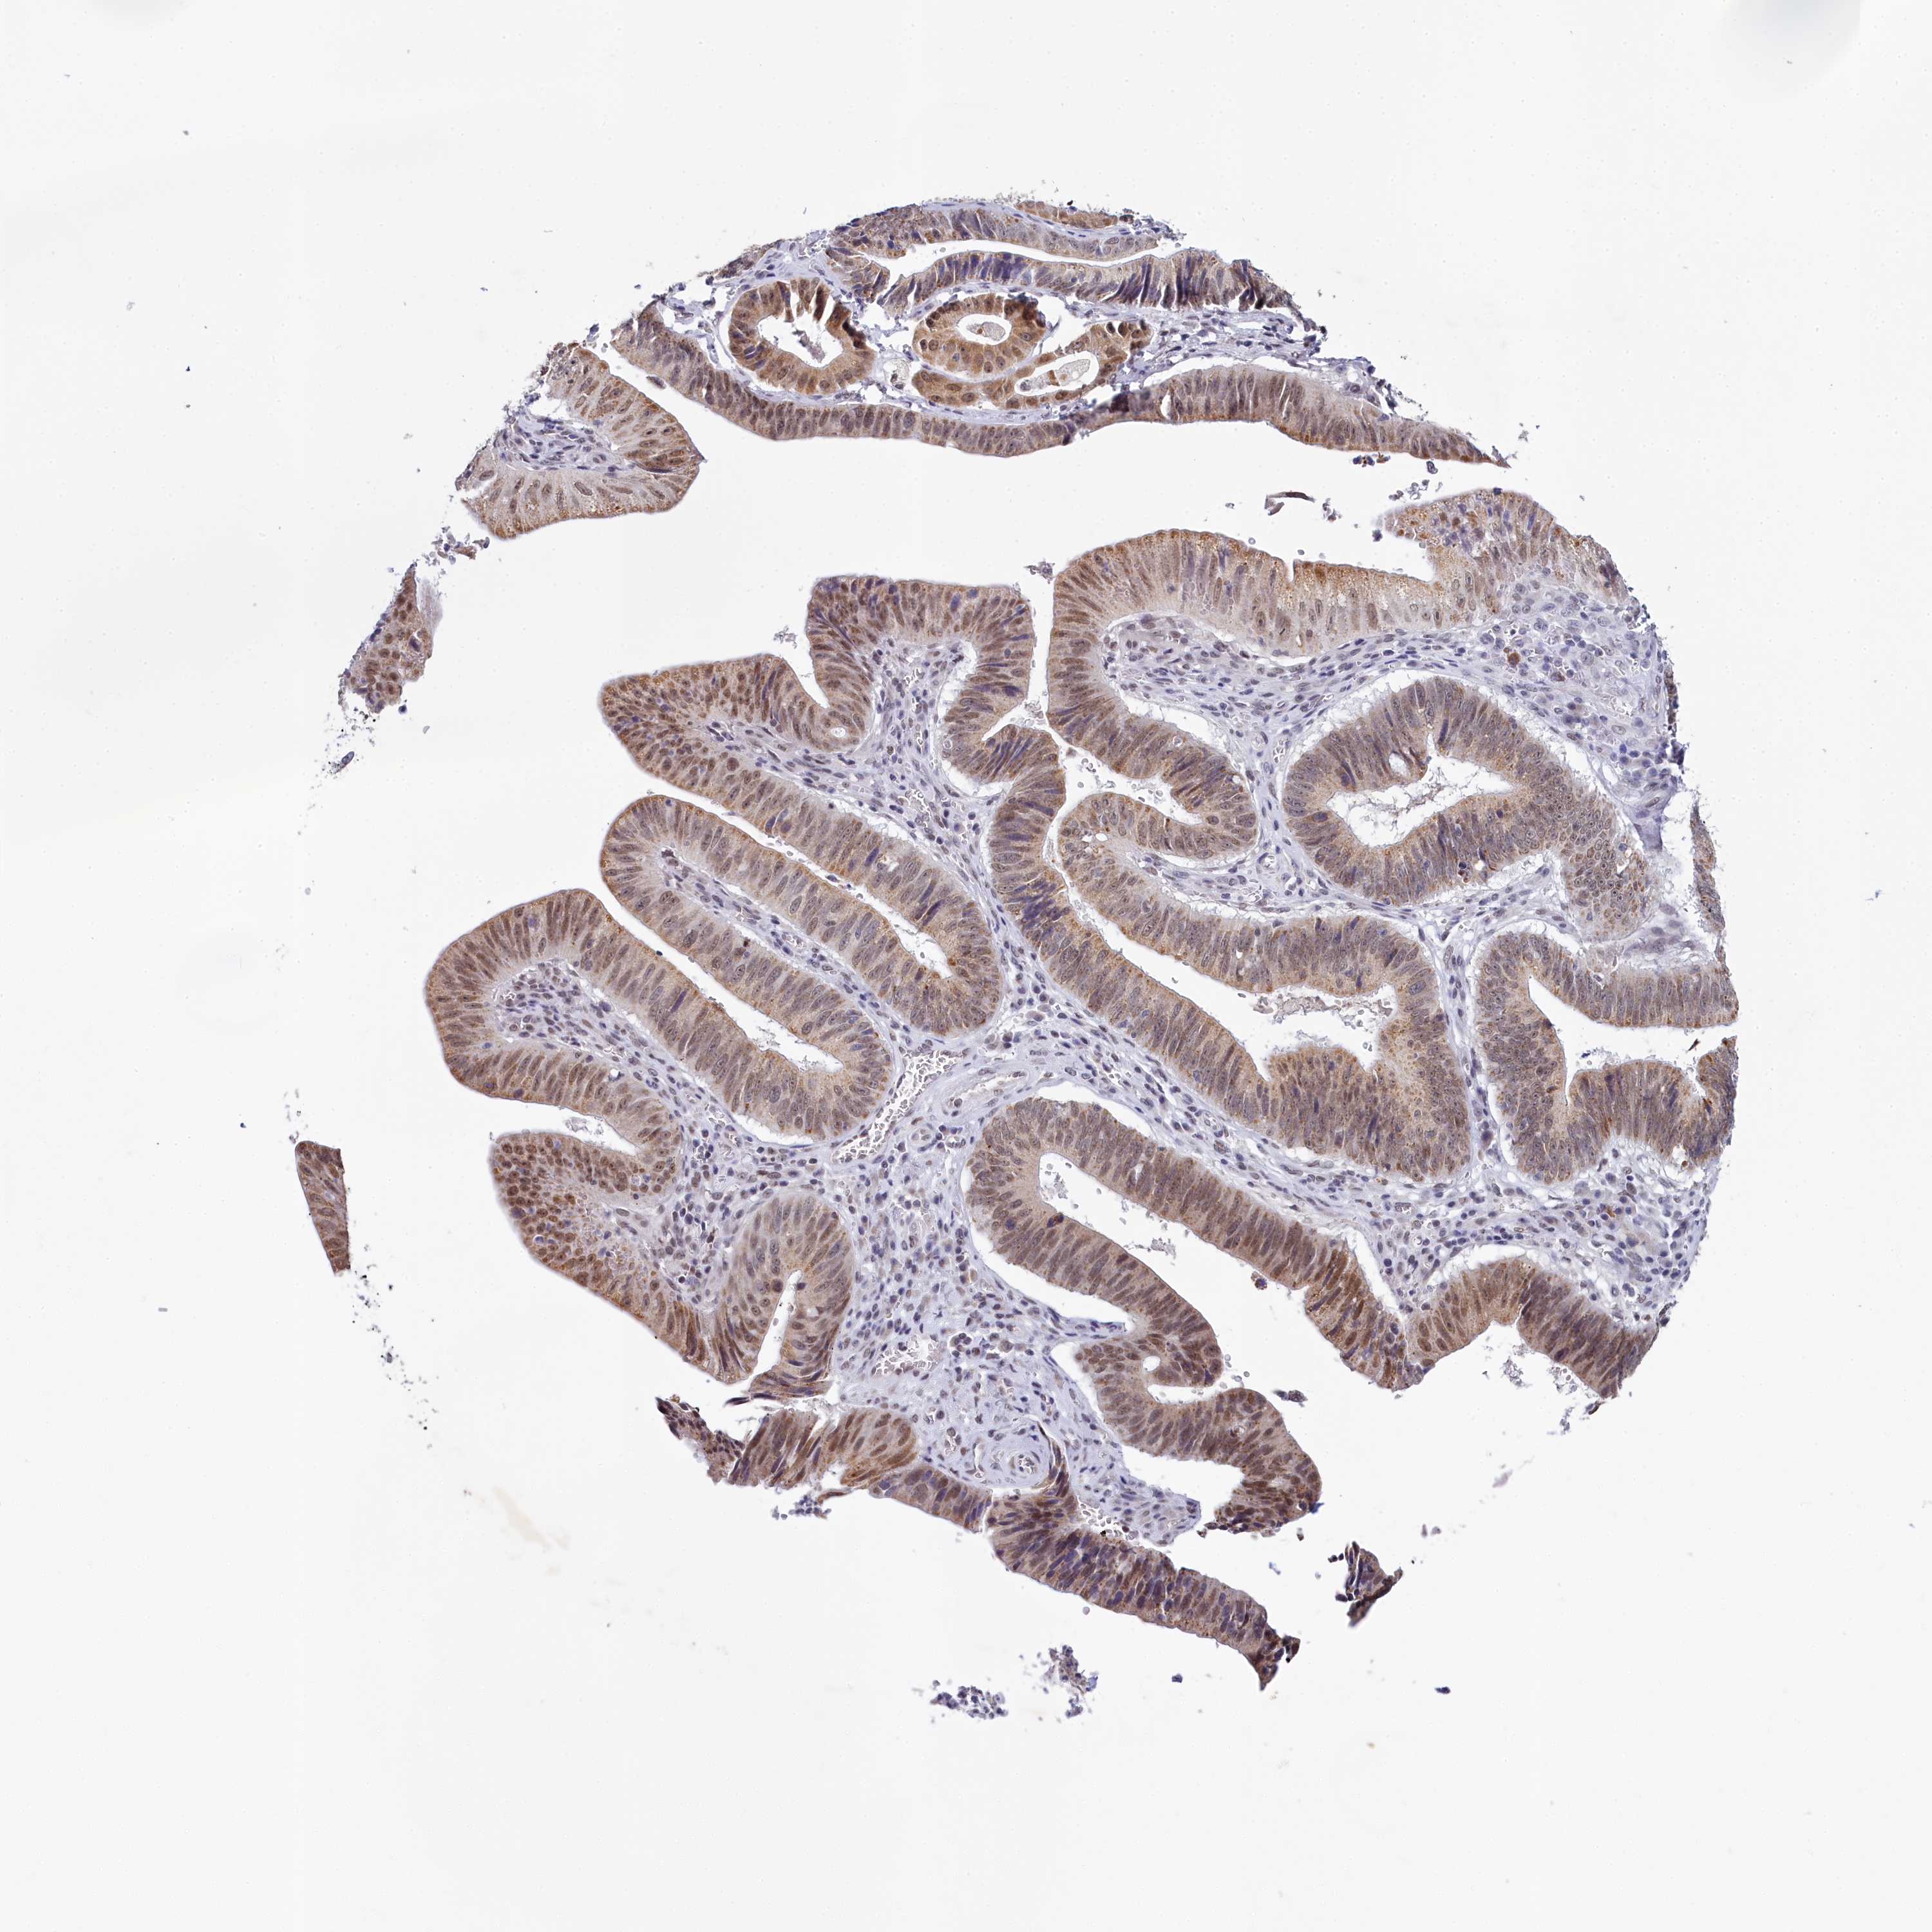

STOMACH CANCER - Protein expressioni

A mouse-over function shows sample information and annotation data. Click on an image to view it in a full screen mode. Samples can be filtered based on level of antibody staining by selecting one or several of the following categories: high, medium, low and not detected. The assay and annotation is described here.

Antibody stainingi

Antibody staining in the annotated cell types in the current human tissue is reported as not detected, low, medium, or high, based on conventional immunohistochemistry profiling in selected tissues. This score is based on the combination of the staining intensity and fraction of stained cells.

Each image is clickable and will lead to virtual microscopy that enables deeper exploration of all samples and also displays staining intensity scores, fraction scores and subcellular localization as well as patient and tissue information for each sample.

Antibody HPA038902

Antibody HPA038903

Staining

High

Medium

Low

Not detected

Intensity

Strong

Moderate

Weak

Negative

Quantity

>75%

75%-25%

<25%

None

Location

Nuclear

Cytoplasmic/membranous

Cytoplasmic/membranous,nuclear

Adenocarcinoma, NOS

Adenocarcinoma, High grade